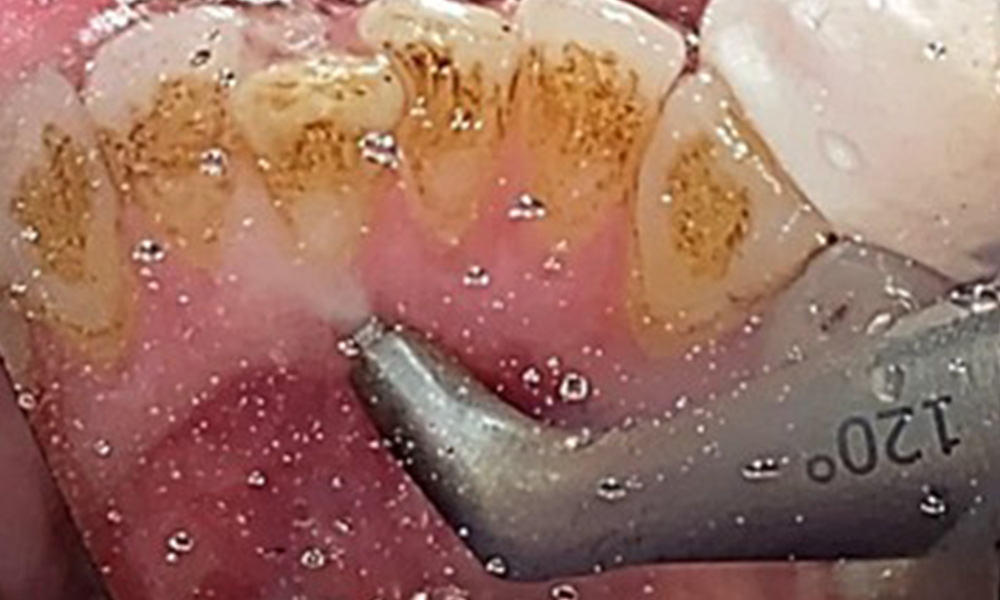

The objective would be to control disease risk by removing supragingival and subgingival biofilm. The instruments can be selected based on patient needs. First, calculus and any concretions must be removed using ultrasonic and/or manual instruments (Fig. 10).

Use of a piezo-driven ultrasonic device in the lingual area near 36

Fig. 10 Use of a piezo-driven ultrasonic device in the lingual area near 36 (Proxeo Ultra, W&H, shown here), © Dr R. Krapf